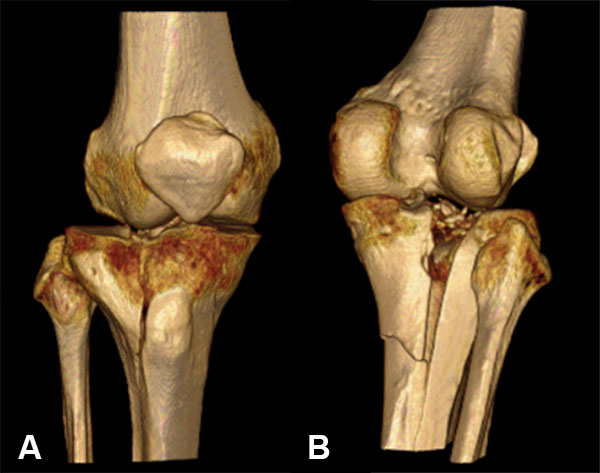

El diagnóstico se realizó siguiendo los hallazgos clínicos, radiográficos, de la tomografía computada o la RMN según el caso (figs. 1 a 7).

Figura 4: Masculino 58 años. Schatzker V.

Figura 5: Masculino 58 años. Schatzker V.

Figura 7: Reconstruccion TAC 3D.